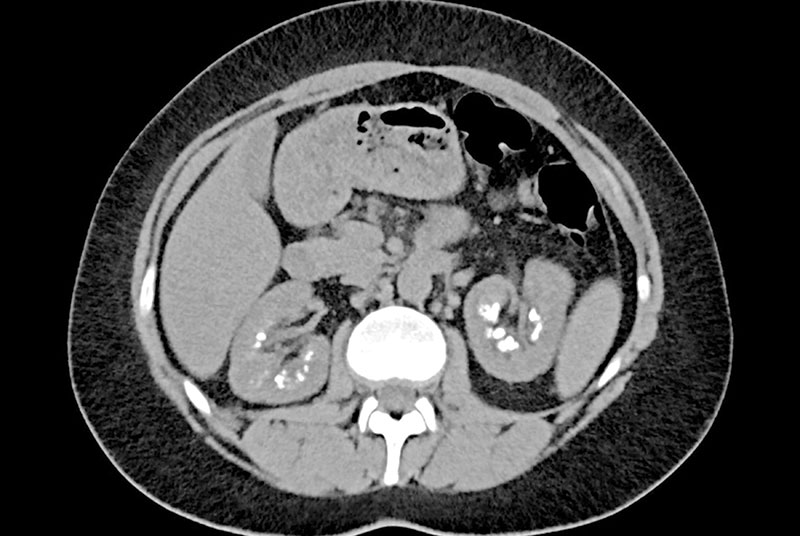

calcification: The process by which calcium salts build up in body tissue, causing the tissue to harden. This often occurs in bones but can also happen in soft tissues as part of disease processes.

calculus: A hard, stone-like deposit formed in a body organ, often referring to kidney stones, gallstones, or dental plaque.

calculi: Plural of “calculus,” referring to small, hard deposits of minerals that can form in various parts of the body, such as kidney stones or gallstones.

calculous: Relating to or characterized by the presence of calculi (stones), especially in the organs or ducts, such as in the gallbladder or kidneys.